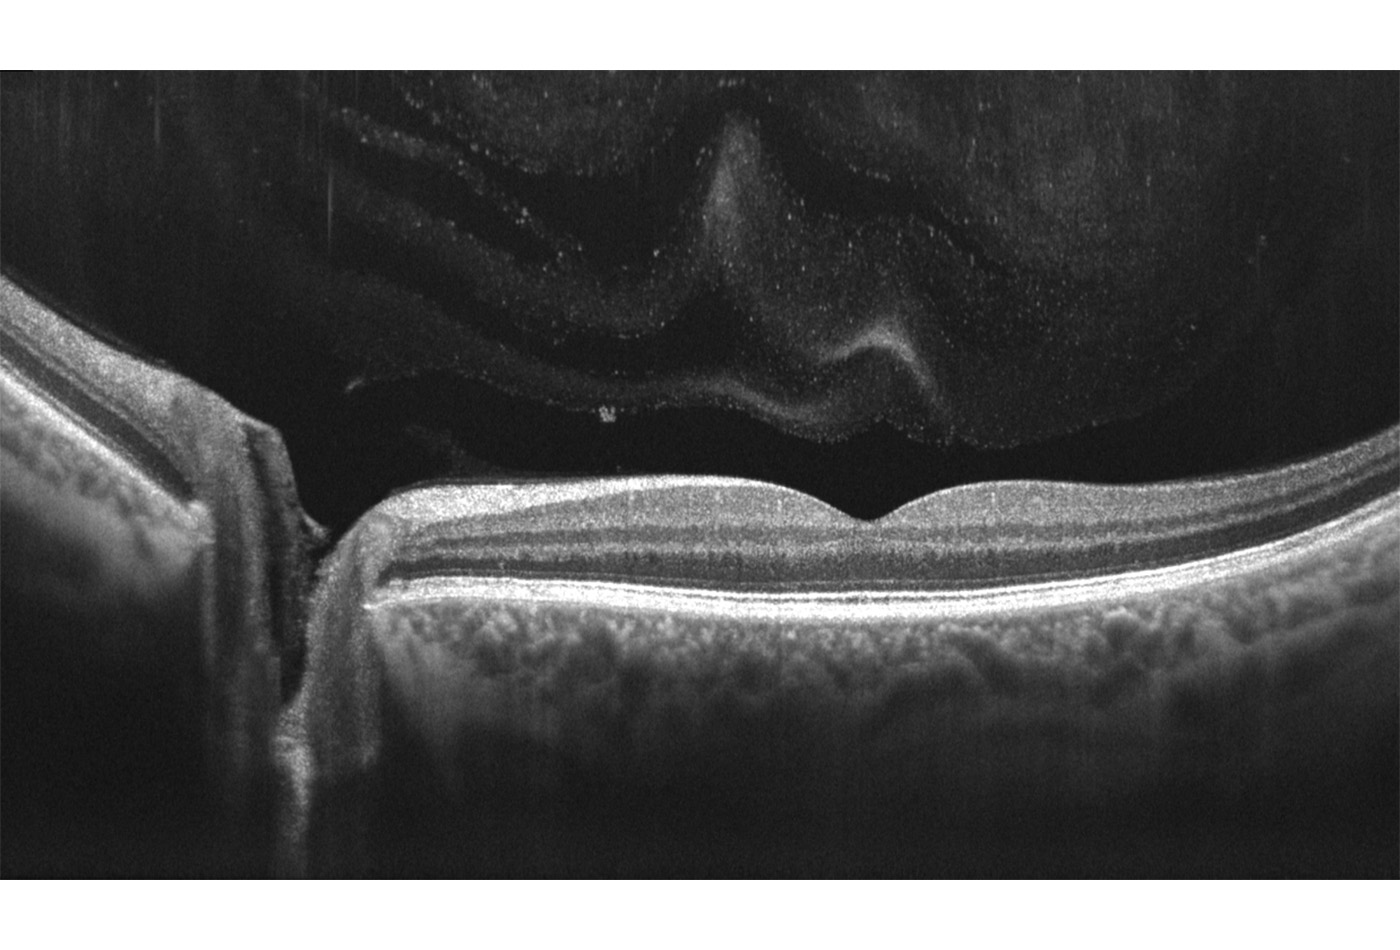

Vorderabschnitt:

- Integriertes Vorderabschnittsmodul (5 X 5mm)

- Autom. Pachymetrie

- Analyse des Kammerwinkels

Optionales Weitwinkelmodul (14 X 5mm):

- Darstellung des vollständigen vorderen Systems

- Messung zweier Kammerwinkel in einer Aufnahme

- Darstellung der Iris

Zusätzlich existiert ein Scanprogramm zur detaillierten Darstellung der Vorderkammer

Anterior:

Pachymetrie

LASIK Flap Vermessung

Kammerwinkelmessung

Weitwinkel-Scans (mit optionalem Weitwinkel-Modul)